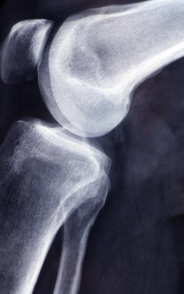

글루코사민 콘드로이친 msm 효능 및 부작용 적정섭취량 알아봐요 글루코사민 콘드로이친 msm 효능 및 부작용 적정섭취량 등 관련 정보 알아보도록 하겠습니다. 관절은 뼈와 뼈 사이에 위치한 연결점으로, 우리 몸을 움직이기 위한 중요한 부분입니다. 관절은 뼈의 끝에 위치한 연골과 뼈를 연결하는 인대로 이루어져 있으며, 이러한 구조는 원활한 움직임을 가능하게 합니다. 하지만 연령이 들어가거나 부상 등으로 인해 관절의 기능이 손상되면 관절염과 같은 질환으로 발생할 수 있습니다. 이러한 질환은 관절 통증, 감각 이상, 염증 및 손상 등을 일으키며, 일상생활에서의 움직임과 활동에 지장을 주어 생활의 질을 저하시킵니다. 이에 따라 적절한 치료와 예방이 필요하며, 영양소와 운동 등을 통한 관리가 중요합니다.

글루코사민은 연골을 유지하는 데 필요한 성분으로, 연골 조직의 생산과 수리를 돕습니다. 또한 관절염 등의 관절 질환으로 인한 통증 및 염증을 완화하는데도 효과적입니다. 또한 연골 조직의 건강을 유지함으로써, 무릎 퇴행성 질환의 발생을 예방하고 뼈 건강에도 도움을 줄 수 있습니다.